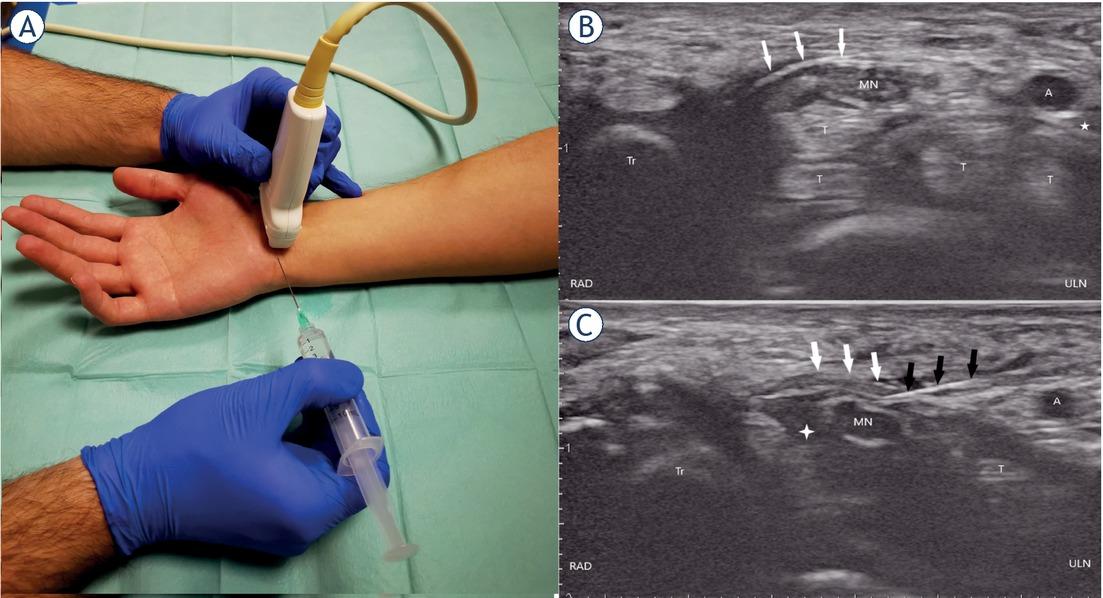

The transducer is positioned at the distal wrist crease perpendicularly to the course of the MN (Figure 2A).13 The probe is then moved ulnarly keeping the MN in view until the pisiform bone, ulnar nerve, and artery are brought into view. On the ulnar side, the pisiform is seen as a hyperechoic structure and the honeycomb appearance of the ulnar nerve may be differentiated radially to the pulsating ulnar artery (Figure 2B).13 The needle is introduced in plane in an ulnar to radial direction, then passes the ulnar nerve and ulnar artery superficially, and punctures the TCL so that the needle tip can be advanced adjacently to the MN (Figure 2C).15,26,27,28

(A), (B), and (C) showing the ulnar approach. (A) wrist and needle positioning for carpal tunnel injection, (B) ultrasound anatomy of the carpal tunnel shown in the short axis, (C) penetrating transverse carpal ligament positioning the needle tip above the median nerve. Ultrasound of the carpal tunnel after the needle penetrates the transverse carpal ligament. Comparing B and C note the expansion of the perineural space marked with a white cross.

A = ulnar artery; black arrows = needle; MN = median nerve; RAD = radial; T = flexor tendons; Tr = trapezium; ULN = ulnar; white arrows = transverse carpal ligament; white cross = perineural injectate; white star = ulnar nerve